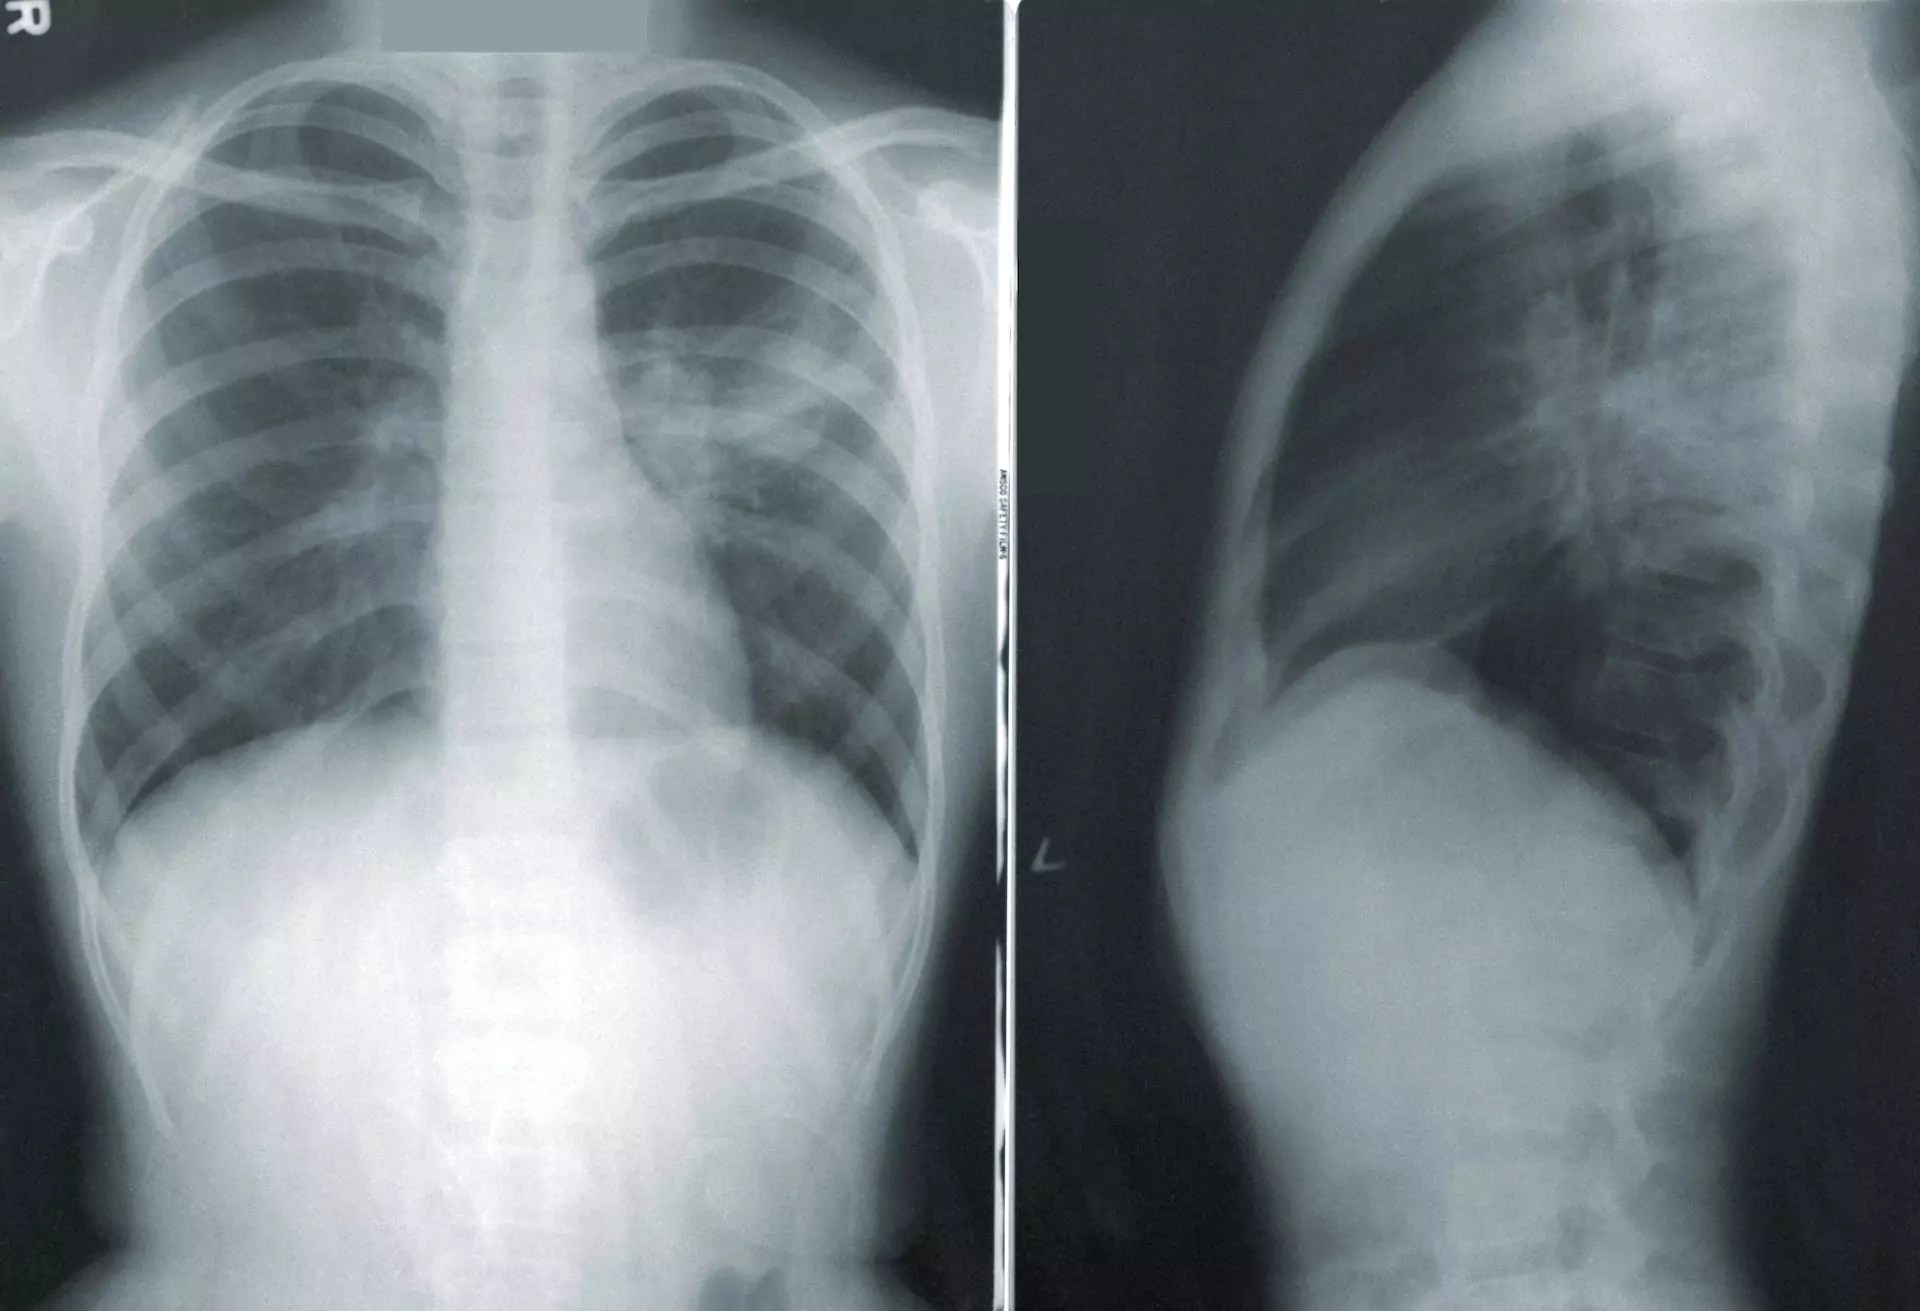

Lobar Pneumonia Chest X Ray Findings malayelly Chest X Ray After Pneumonia Treatment Your doctor will start by asking. The british thoracic society (bts) recommend follow up. Introduction it has become regular practice to arrange repeat cxrs for patients diagnosed with cap. Malignancy and other important nonmalignant pulmonary diseases may present with a radiographic appearance similar to pneumonia. Chest X Ray After Pneumonia Treatment.